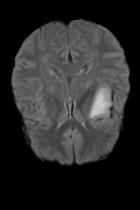

Current unsupervised anomaly localization approaches rely on generative models to learn the distribution of normal images, which is later used to identify potential anomalous regions derived from errors on the reconstructed images. However, a main limitation of nearly all prior literature is the need of employing anomalous images to set a class-specific threshold to locate the anomalies. This limits their usability in realistic scenarios, where only normal data is typically accessible. Despite this major drawback, only a handful of works have addressed this limitation, by integrating supervision on attention maps during training. In this work, we propose a novel formulation that does not require accessing images with abnormalities to define the threshold. Furthermore, and in contrast to very recent work, the proposed constraint is formulated in a more principled manner, leveraging well-known knowledge in constrained optimization. In particular, the equality constraint on the attention maps in prior work is replaced by an inequality constraint, which allows more flexibility. In addition, to address the limitations of penalty-based functions we employ an extension of the popular log-barrier methods to handle the constraint. Comprehensive experiments on the popular BRATS'19 dataset demonstrate that the proposed approach substantially outperforms relevant literature, establishing new state-of-the-art results for unsupervised lesion segmentation.